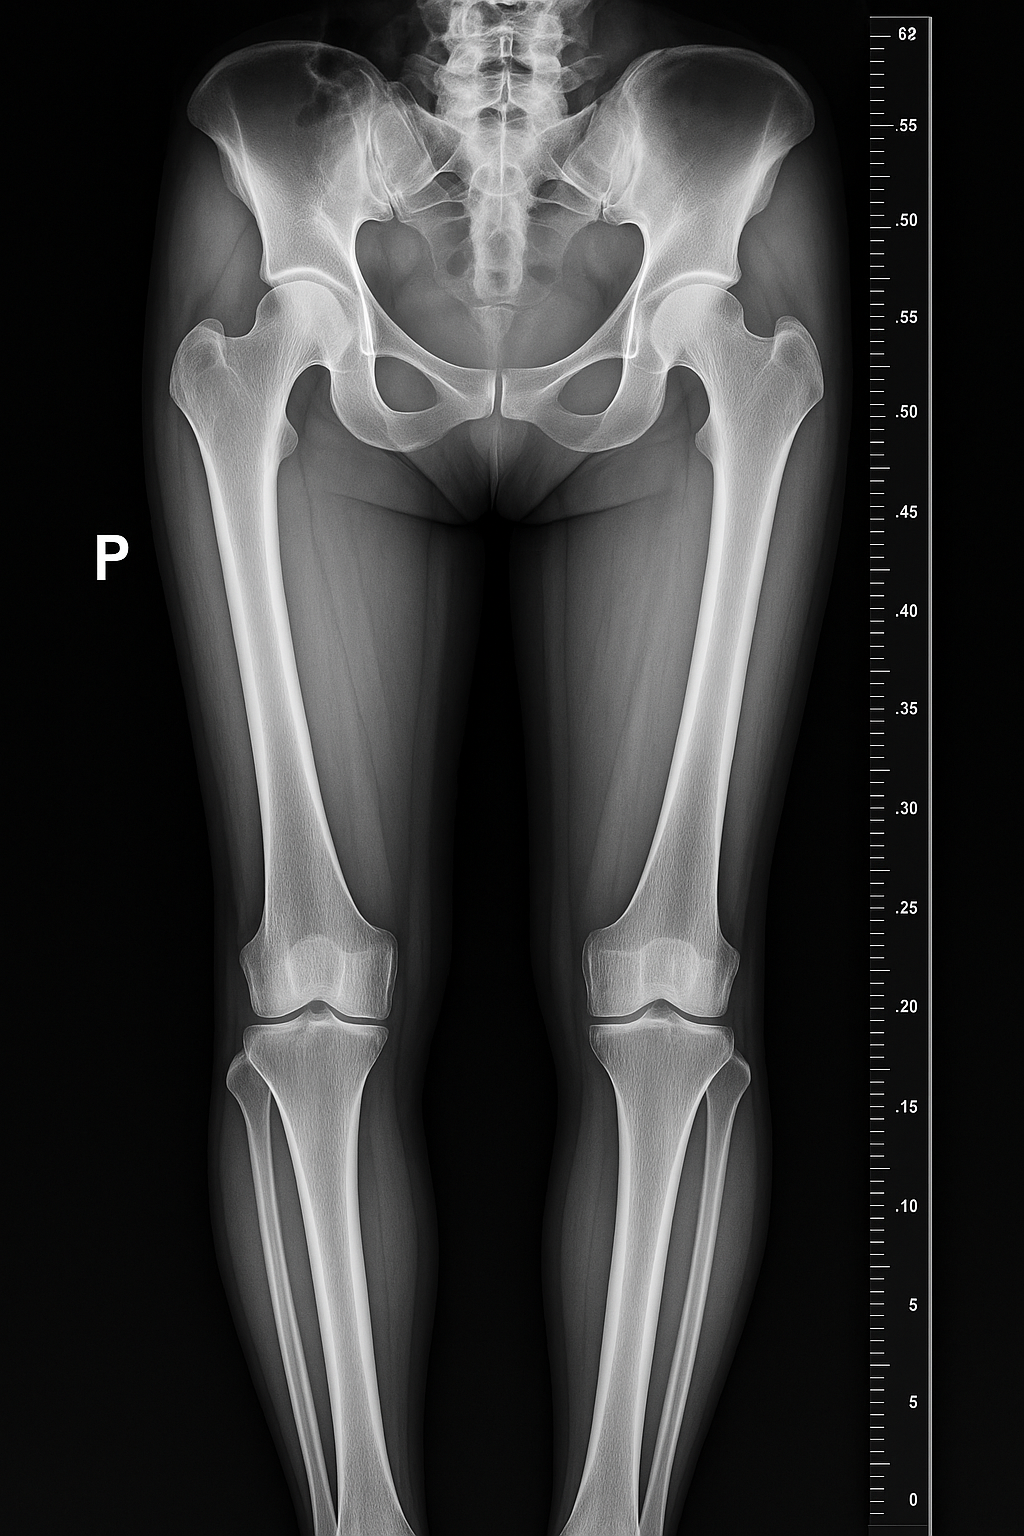

Nowoczesna pracownia RTG

Oferujemy szybką i precyzyjną diagnostykę obrazową w komfortowych warunkach. Nasza pracownia wyposażona jest w najnowszy system cyfrowy, gwarantujący najwyższą jakość przy minimalnej dawce promieniowania.